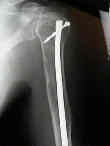

Fijación

quirúrgica:

El enclavado IM femoral profiláctico:

Radioterapia:

El mieloma es sensible a la radioterapia, y la reosificación de los defectos del tumor pueden ocurrir dentro de varios meses.